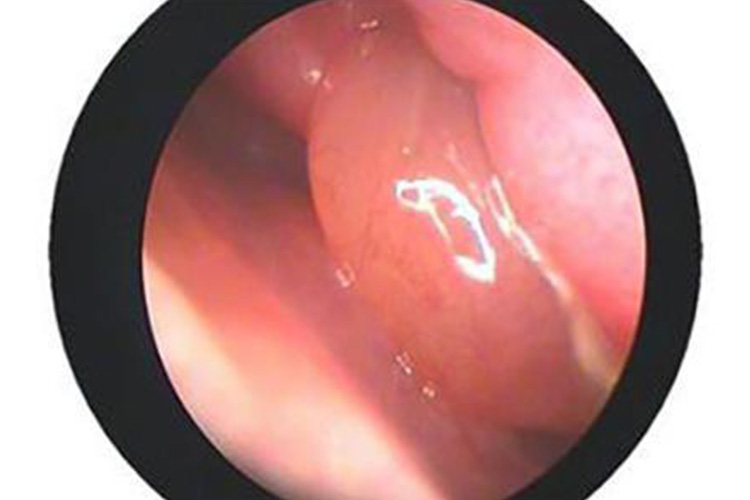

伴鼻息肉的慢性鼻窦炎:此类患者常表现为双侧进行性鼻塞,伴有清涕或黏性鼻涕,部分患者伴有嗅觉减退、头面部闷胀沉重感。